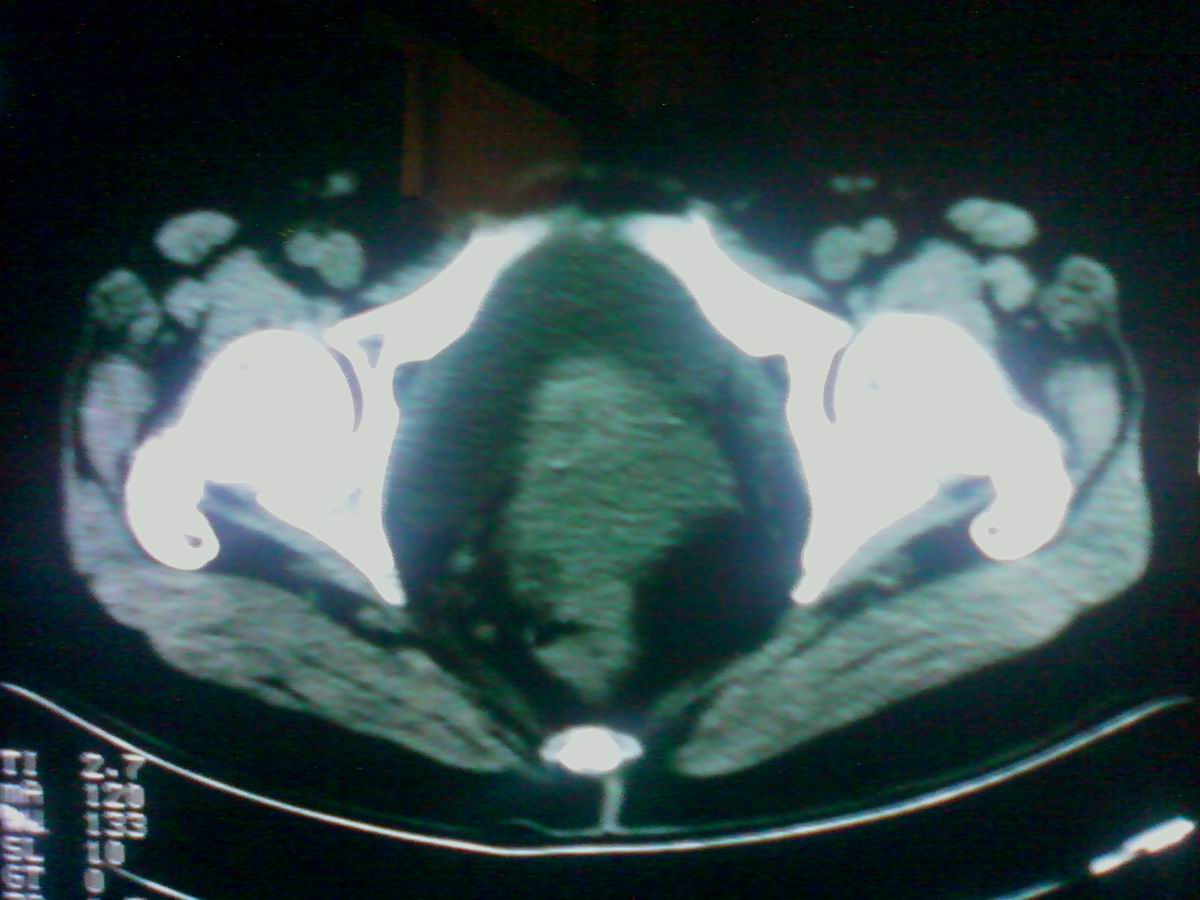

标题: CT25799:女性患者,45岁,腹胀,上腹部疼痛来诊,B超示盆腔 [打印本页]

标题: CT25799:女性患者,45岁,腹胀,上腹部疼痛来诊,B超示盆腔

考虑卵巢癌伴腹水

1)考虑卵巢恶性肿瘤。2)腹水。